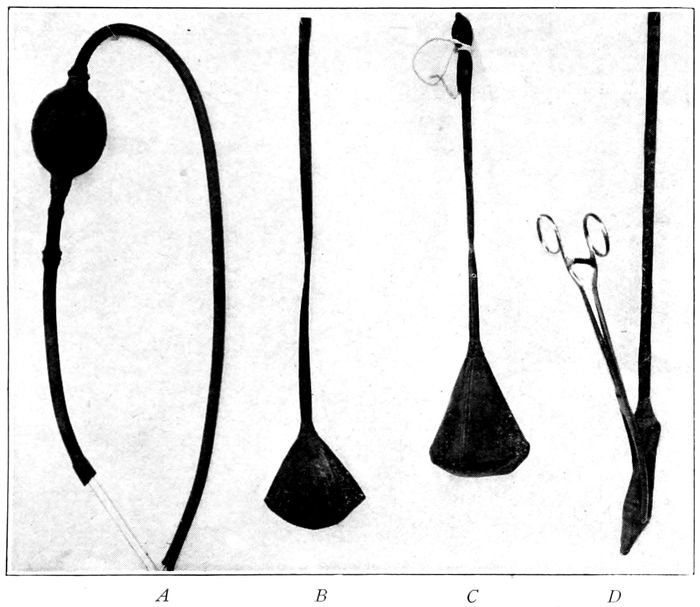

208 |

| 90. |

209 |